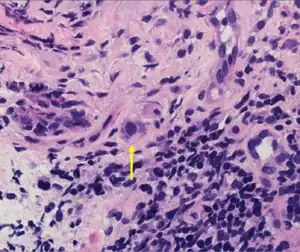

| Typical "owl eye" intranuclear inclusion indicating CMV infection of a lung pneumocyte[1] | |

- ↑ Mattes FM, McLaughlin JE, Emery VC, Clark DA, Griffiths PD (August 2000). "Histopathological detection of owl's eye inclusions is still specific for cytomegalovirus in the era of human herpesviruses 6 and 7". Journal of Clinical Pathology. 53 (8): 612–4. doi:10.1136/jcp.53.8.612. PMC 1762915. PMID 11002765.